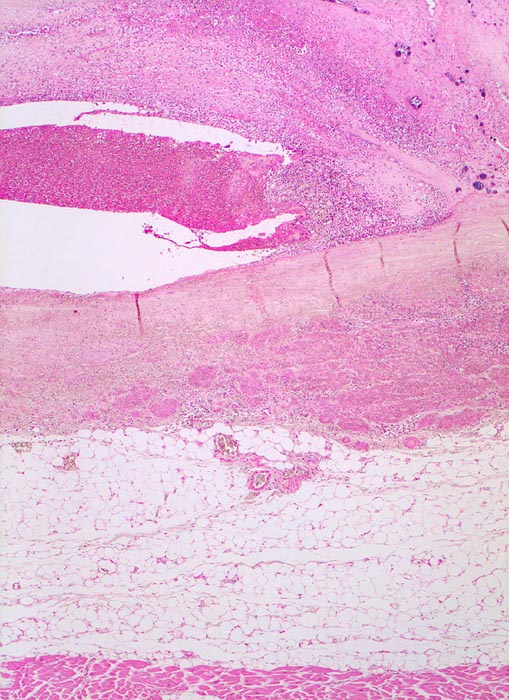

Histologisch findet sich bei ulzeropolypöser Endokarditis ein Fibrin-Thrombozytenthrombus, welcher von Bakterien durchsetzt ist (=Vegetation). Die Vegetation sitzt auf einem Klappendefekt an dessen Basis Granulationsgewebe einzusprossen beginnt, welches den Thrombus organisiert. Klappendefekte, Gefässeinsprossungen, verdickte Sehnenfäden (> 2848) oder Kommissurenverwachsungen (> 8389) der Taschenklappen weisen morphologisch auf eine abgeheilte Endokarditis hin.

• Längsschnitt durch Aorta, Aortenklappe und linkes Ventrikelmyokard.

• Ausgedehnte frische Koagulationsnekrose (unsichtbare Zellkerne, Infiltrate neutrophiler Granulozyten) des linken Ventrikelmyokards unterhalb der Klappe.

• Mehrere septikopyämische Streuherde (blaue Bakterienhaufen in intramyokardialen Blutgefässen umgeben von Mikroabszessen).